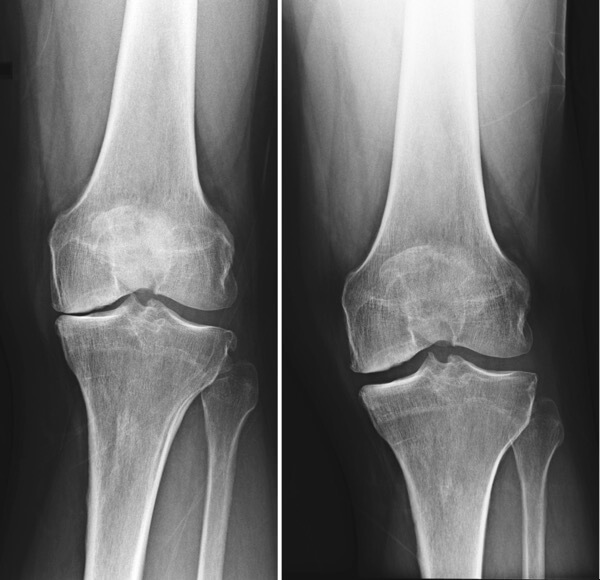

Aterosklerozės pažeisto kelio sąnario atstatymas. Pacientui po mėnesio naudojimo buvo visiškai atkurti sąnario struktūra ir paslankumas. Skausmas visiškai išnyko.